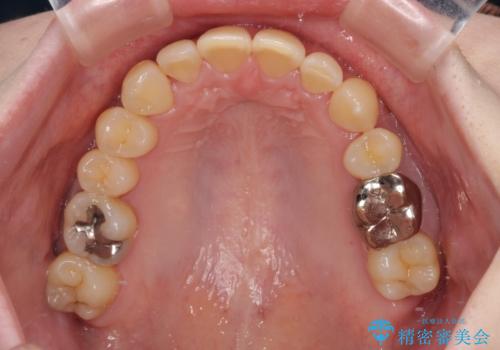

- 八重歯と正中のズレを気にして来院された患者様です。

上顎左側が八重歯になっており、上顎正中が左側にずれていました。

上顎左側の第一小臼歯を抜歯し、補助装置を用いて正中位置を改善しながら八重歯を解消していくこととしました。

下顎前歯が1本欠損していたため、上下正中の位置が合わせるという目標はなく、鼻筋に上顎正中を合わせていくように移動を行いました。